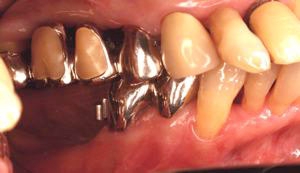

片側2歯欠損片側2歯欠損片側2歯欠損 主訴-入れ歯を使ってみたが違和感強くてダメ。固定のものにしたい。術前下顎口腔内(鏡像) 二次オペ時(鏡像)二次オペ時(鏡像)二次オペ時(鏡像) 術後術後術後、左下奥2本インプラント(鏡像) 術後(レントゲン)術後(レントゲン)術後(レントゲン)、左下奥2本インプラント